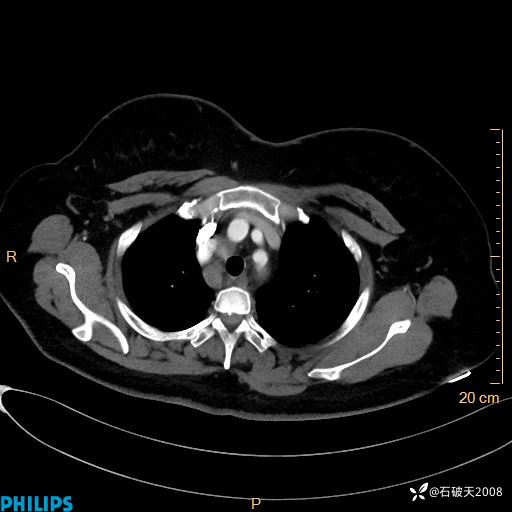

肺窗

纵隔窗